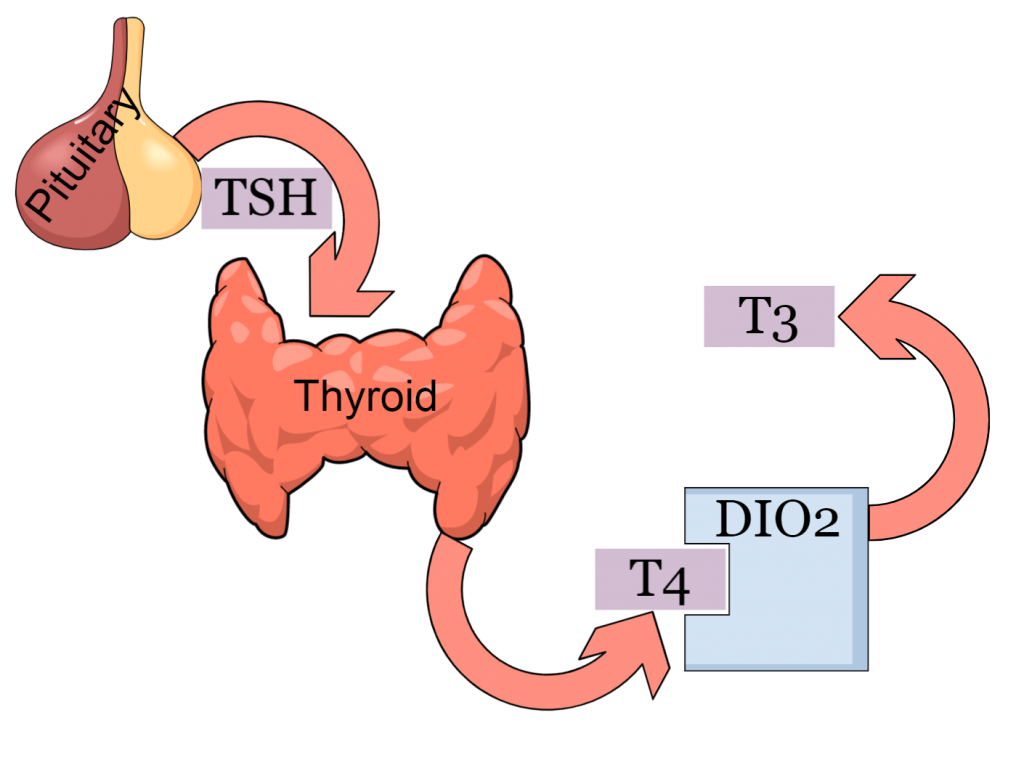

Hashimoto’s disease may induce low stomach acid, making food preparation different and prolonging passage

- Hashimoto's thyroiditis may directly interfere with the Migrating Motor Complex which is crucial for small intestinal cleaning after meals

Katherine’s results revealed a very intense SIBO produced gas signal along with a deeply disordered microflora. Besides commensal microbes whose levels were diminished, two Citrobacter species were detected in pathogenic amounts. Two many protein fragments were recovered on stool whereas several vitamin and nutrient deficiencies could be attributed to malabsorption. Finally, zonulin was recovered in very high levels indicating augmented intestinal permeability. Hashimoto’s and leaky gut are part of a vicious cycle. Thyroiditis delays MMC, leading to SIBO which in turn increases intestinal permeability and permits food antigens to get into circulation.